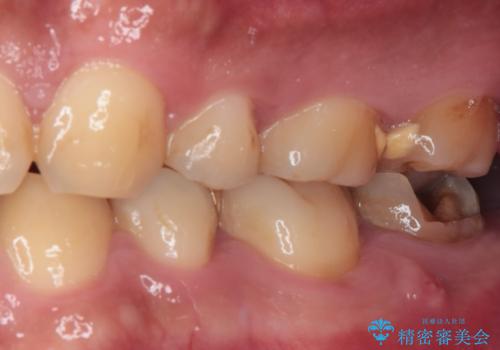

伸び出してきた上顎奥歯 部分矯正を用いた奥歯の補綴治療

- 下顎奥歯のむし歯治療を希望して来院された患者様です。

対合の上顎の奥歯は、むし歯で欠損した部分と咬み合うように伸び出してきていました。

下顎のむし歯の範囲が広く、既に神経は失活しており、根管治療が必要な状態でした。

上顎の歯をアンカースクリューを用いた部分矯正により位置を修正し、根管治療後にPGAクラウンにて補綴治療を行うこととしました。